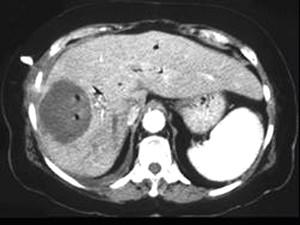

问题 男,48岁,寒战高热,右上腹痛一天,CT检查如图所示,最可能的诊断是 ( )

选项 A、肝错构瘤 B、肝转移瘤 C、肝脓肿 D、胆管细胞癌 E、原发性肝癌 单选题

答案 C